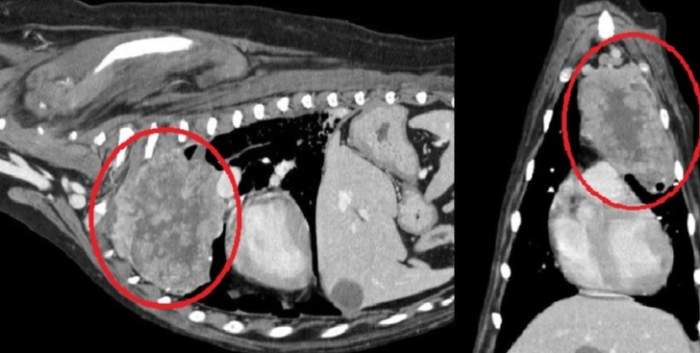

診斷過程通常需要多管齊下。獸醫可能會先聽診,然後建議做X光或超音波。X光是最基本的工具,可以看肺部的陰影變化。但如果腫瘤很小,X光可能看不出來,這時就需要進階檢查如CT掃描。

| 進階診斷 | CT掃描、活檢 | 確認腫瘤位置和類型 |